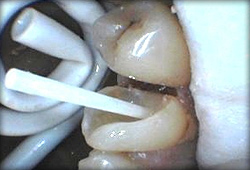

Or maybe composite restoration with a fiberglass reinforcement